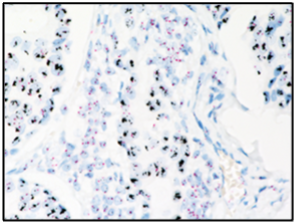

使用VENTANA HER2 Dual ISH DNA Probe Cocktail檢測法檢測HER2基因擴增狀態(tài)

據(jù)悉,該檢測可在羅氏診斷BenchMark ULTRA全自動免疫組化染色系統(tǒng)上實現(xiàn)全自動化運行,有效確保檢測的質(zhì)量和效率。在結(jié)果判讀上,僅使用普通光學(xué)顯微鏡就能隨時、精準觀察組織形態(tài)和信號狀態(tài),此外,染色切片還可長期保存,便于結(jié)果查閱、復(fù)審及疑難病例討論 ,全面滿足病理實驗室規(guī)范化、標準化檢測的需求。